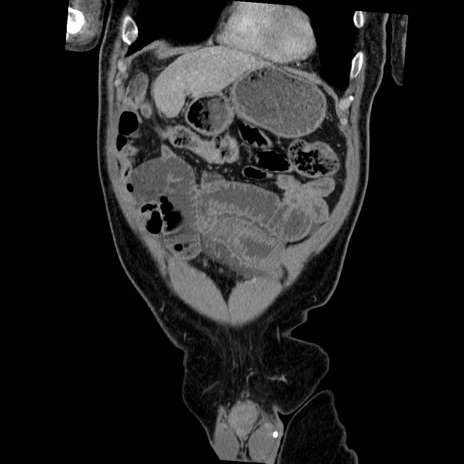

症例22(冠状断像)

【症例】50歳代男性

【主訴】腹痛

【現病歴】AVMからの被殻出血のため回復期リハ病棟入院中。 本日午後3時頃急に下腹部痛が出現した。

【既往歴】AVM、被殻出血、虫垂炎、高血圧

【身体所見】意識晴明、左半身不全麻痺、会話の理解は良好、36.5°C、腹部:膨隆、全体に板状硬、下腹部正中に圧痛点あり、反跳痛-、筋性防御不明、右下腹部にope scar

【データ】WBC 9400、CRP 0.06